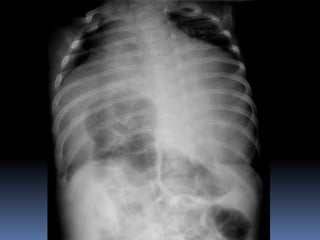

PROYECCION SIMPLE DE

ABDOMEN

CRITERIOS DE EVALUACION

P.S.A.

 Apreciar desde el

abdomen superior hasta

la sínfisis del pubis.

 Lumbares, pelvis y

ultimas costillas sin

rotación.

 Apófisis espinosas en el

centro de cuerpos

vertebrales.

 Ver el bazo, riñones,

psoas y “borde inferior

hepático

CRITERIOS DE EVALUACION P.S.A.  Apreciar desde el abdomen superior hasta la sínfisis del pubis.  Lumbares, pelvis y ultimas costillas sin rotación.  Apófisis espinosas en el centro de cuerpos vertebrales.  Ver el bazo, riñones, psoas y “borde inferior hepático

INTERPRETACION  Estructuras óseas (densidades).  Tejido blando  Psoas.  Bazo  Niveles Hidroareos.  I.D.  Colon  Silueta Renal